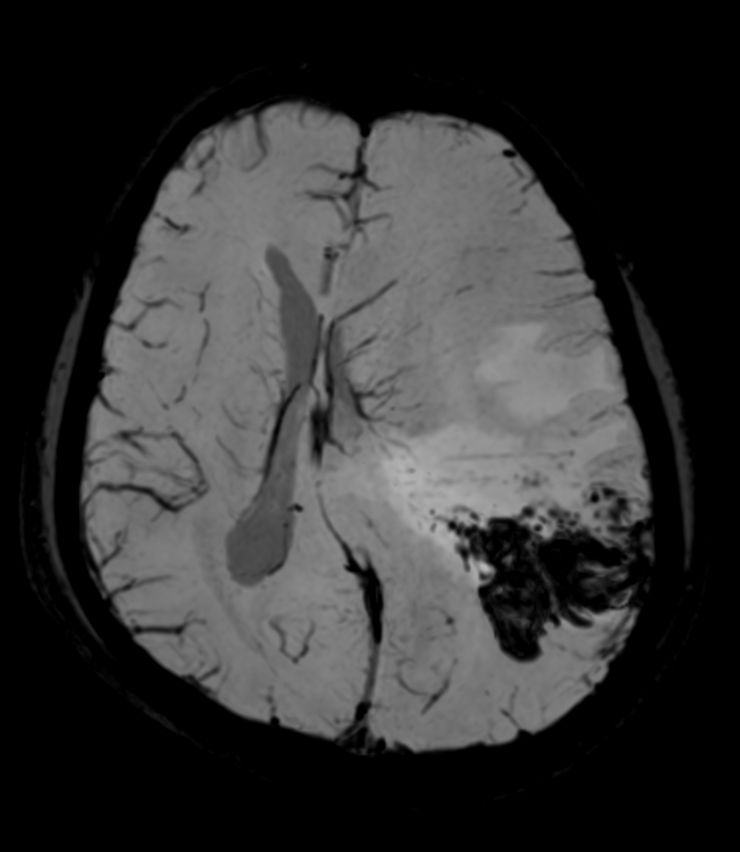

Pediatric Brain with hemorrhagic mass

Pediatric patient with a hemorrhagic mass in the brain